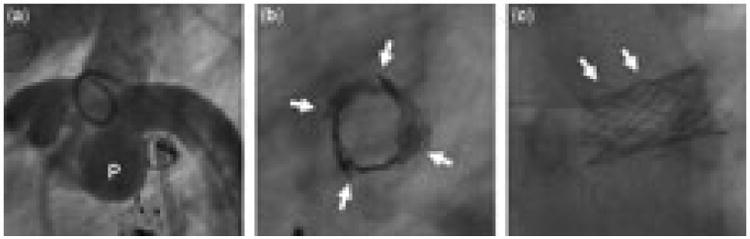

Figure 2.

This stent was placed in the central left pulmonary artery, in the crook of the reconstructed aortic arch, in a patient with double inlet left ventricle who had previously undergone reconstruction of the aortic arch. (a) The native pulmonary root (P) is large and directly apposed to the stented left pulmonary artery, and the arch is pulled down and anteriorly by the reconstruction, such that the normal space beneath the arch is smaller than usual. (b) In the lateral projection, four axial fracture planes, with overlapping edges, can be appreciated clearly (arrows). The stent collapsed inward around its circumference, and the fractured edges overlap in such a manner that the stent retains a relatively cylindrical geometry, in contrast to the anteroposterior collapse of the stents in Figure 1. (c) From a left anterior oblique projection, the fracture is not as readily apparent, although disarticulated struts can be seen along the superior margin of the stent (arrows).

In our experience, in situ fracture of stents used to treat central pulmonary arterial stenosis is relatively common. Although the design of our study does not allow a true estimate of the incidence of fracture, or of time to failure of the initial stent, we found that, of pulmonary arterial stents evaluated by catheterization at least 3 years after placement, one-fifth were fractured. Pulmonary arterial stents implanted in environments exposed to large cyclic external compressive forces appear to be particularly susceptible to fracture. Stents juxtaposed to the ascending aorta, most often in the central right pulmonary artery, posterior to the ascending aorta, had the highest risk of fracture. Larger stents, both in length and deployed diameter, were also more prone to fracture, which may speak to environmental effects resulting in an increased likelihood of compression, or to stent-related factors such as size- dependent differences in biomechanics. Patient-related factors associated with higher risk of fracture included a diagnosis of common arterial trunk or transposition after an arterial switch operation, and the presence of a right aortic arch. These factors are most likely important because of their association with increased risk of pulmonary arterial compression. For example, the space between the ascending and proximal descending aorta may be relatively small when the aortic arch is right-sided, or in patients with a particularly large aortic root or ascending aorta, as is often seen in association with common arterial trunk (Fig. 1), which may increase the likelihood of compression of the right pulmonary artery. Similarly, after the arterial switch operation with the Lecompte manoeuvre, the branches of the pulmonary trunk may be draped around, and consequently subject to compression by, the ascending aorta (Fig. 3). In fact, 4 of the 11 fractured stents in the central left pulmonary artery in this series were in patients who had undergone an arterial switch operation. Other circumstances in which stents in the left pulmonary artery fractured were in patients with tetralogy of Fallot, in whom the angle of origin of the left pulmonary artery from the pulmonary trunk is abnormally acute and prone to kinking, and in patients with functionally univentricular disease who had undergone reconstruction of the aortic pathway, and subsequently developed compression and stenosis of the central left pulmonary artery by the large neo-ascending aorta anteriorly (Fig. 2).

The manifestations of fracture may vary considerably. The effect of fracture and compression on luminal size and haemodynamic obstruction is a function both of the relief of stenosis from angioplasty and stenting in the first place, and the cross-sectional area of the lumen. When exposed to very high or complex multiaxial compressive forces, a fractured stent may collapse almost completely, or fracture along multiple planes, resulting in a vascular cross-section that takes a lenticular shape (Fig. 1). Severe eccentricity was observed in one-fifth of fractured stents, and in three-tenths of cases there was severe obstruction of the stented pulmonary arterial segment (Fig. 3). On the other hand, most of the fractures identified were associated with modest collapse and mild obstruction. In some of these cases, the compressive forces acting on the stent may be such that very little deformation of the cross-sectional geometry occurs once the point of plastic deformation has been reached, and in others, the fractured edges of the stent overlap, with the contour of the separate segments remaining more or less intact, resulting in a relatively circular cross-sectional area, only with a smaller diameter (Figs. 2 and 4).